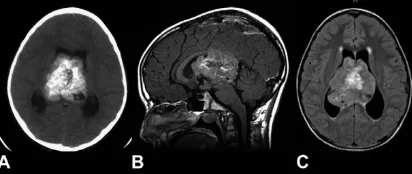

48岁男性患者因头痛加剧伴视物模糊3天就诊。术前影像学检查显示窦汇区存在约11.5厘米的轴外占位性病变,增强扫描呈现明显强化特征。脑血管造影检查证实病变导致上矢状窦、窦汇及左侧横窦近...

室管膜瘤属于胶质肿瘤范畴,颅内室管膜瘤好发于第四脑室,起源于第四脑室底部室管膜细胞的肿瘤性转化。肿瘤常向蛛网膜下腔延伸,有时可包裹延髓和上段颈髓。幕上室管膜瘤可位于脑室内(...